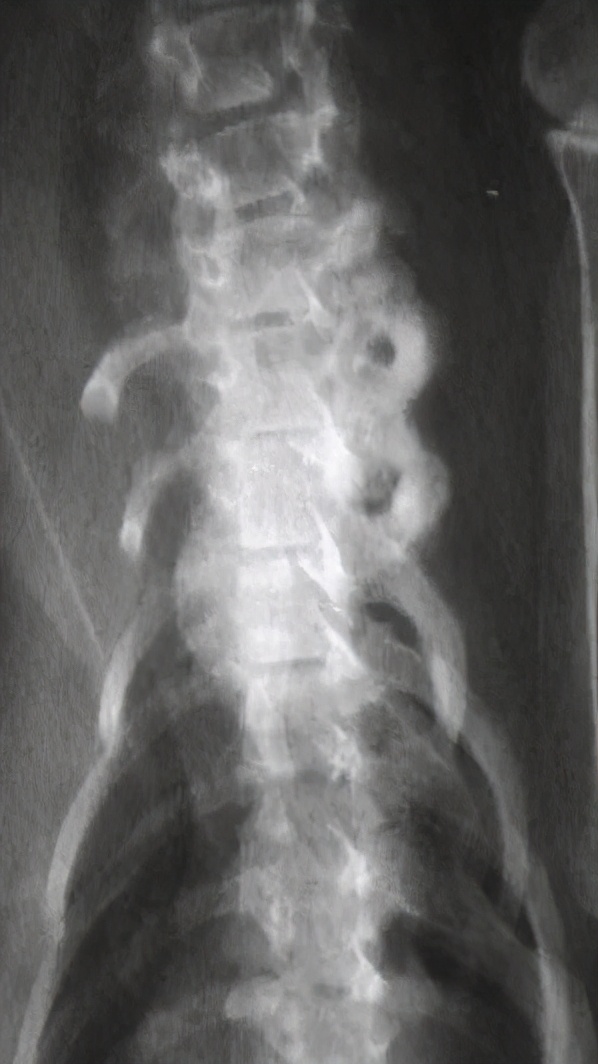

九岁 去势 公猫,长期以猪肝为主喂食自制食物。就诊时左前肢跛行,后出现霍纳氏综合征,两个月发展成瘫痪。

经病史检查,血液和影像学分析和以及血清维生素A浓度的测定,诊断为维生素A过量继发 臂 神经丛压迫。

尾颈椎和颅胸椎腹侧新骨形成